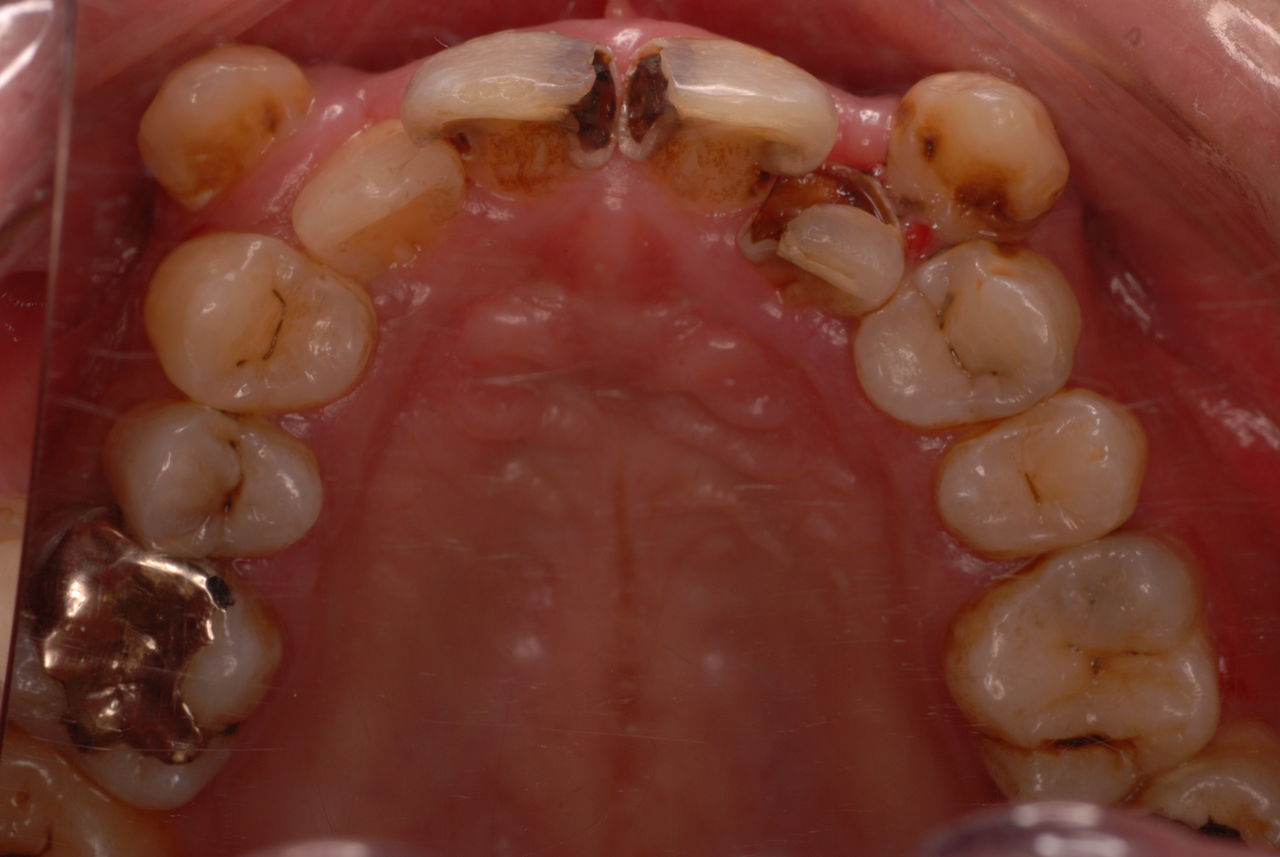

30代の男性の方です。

入れ歯を入れていました。歯科医院で歯を抜けず仕方なく入れ歯にしたとか。何とかならないものだったのか悔やまれました。

抜いた歯はありません。

一応差し歯にしましたが、歯茎の状態はよくはありません。

とりあえず希望を入れて差し歯にしたような感じです。